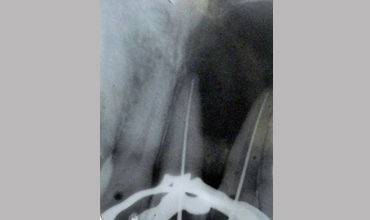

Surgical Management Of Large Periapical Cyst